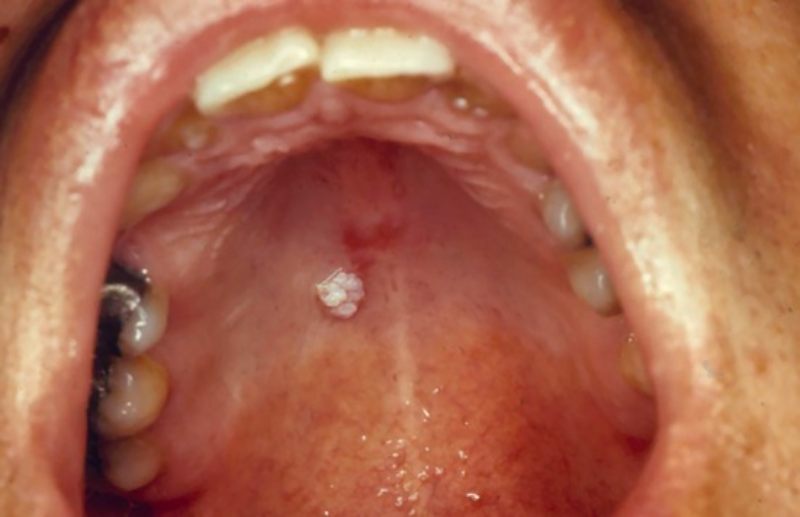

Dấu hiệu đặc trưng nhất của sùi mào gà ở khoang miệng là sự xuất hiện của các nốt sùi màu hồng hoặc trắng, bề mặt mềm, có thể hơi ẩm, kích thước thường nhỏ dưới 1 cm và nổi gồ trên niêm mạc. Những nốt này có thể mọc đơn lẻ hoặc kết thành cụm, tạo hình dạng giống mào gà hoặc hoa súp lơ. Một số tổn thương, đặc biệt dạng u nhú vảy, có hình “ngón tay” nhỏ hoặc có cuống.

Các nốt sùi thường không gây đau, nhưng dễ bị xây xước và chảy máu khi ăn uống hoặc đánh răng. Vị trí thường gặp gồm niêm mạc môi, viền đỏ môi, mặt bên lưỡi, thắng lưỡi, niêm mạc má, khẩu cái mềm hoặc vòm miệng.